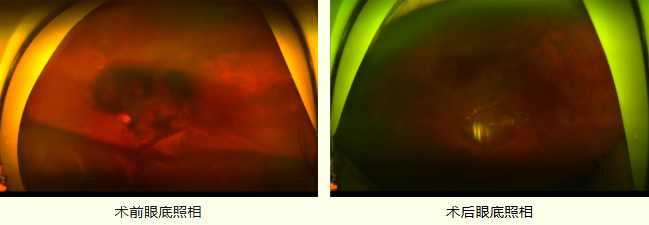

? ?近日,濟(jì)南明水眼科醫(yī)院完成一項(xiàng)新技術(shù),視網(wǎng)膜下 t-PA(阿替普酶)藥物注射治療PCV(息肉樣脈絡(luò)膜視網(wǎng)膜病變)并發(fā)癥黃斑出血的患者,術(shù)后視力明顯好轉(zhuǎn),彰顯了我院眼科團(tuán)隊(duì)在疑難病例治療的合實(shí)力。

姜先生因“左眼視物不清半個(gè)多月,加重5天”來(lái)我院門(mén)診就診。經(jīng)檢查,姜先生視力已經(jīng)下降到CF/20cm,診斷為“PCV(左)、黃斑出血(左)、出血性視網(wǎng)膜脫離(左)”,PCV合并黃斑下出血、出血性視網(wǎng)膜脫離嚴(yán)重影響視力,且黃斑區(qū)是中心視力的關(guān)鍵區(qū)域,若不盡快清除黃斑下積血,血液中的含鐵血黃素會(huì)對(duì)感光細(xì)胞造成嚴(yán)重的不可逆損傷,治療難度極大。

面對(duì)復(fù)雜的病情,我院眼底病科主任韓彥輝,經(jīng)過(guò)詳細(xì)檢查和術(shù)前研討,決定給予患者“左眼微創(chuàng)玻璃體切割+視網(wǎng)膜下t-PA注射+鞏膜外穿刺放液術(shù)”的綜合治療方案,最大限度的挽救姜先生視力。

術(shù)中患者的左眼玻璃體切除干凈,將一根細(xì)如發(fā)絲的41G超精細(xì)針頭刺入黃斑厚度不足0.2毫米的視網(wǎng)膜,多點(diǎn)注射溶栓藥物t-PA,待藥物開(kāi)始溶解積血后,于鞏膜外切開(kāi),行鞏膜外穿刺放液,將視網(wǎng)膜下出血放出,整個(gè)手術(shù)過(guò)程順利,術(shù)中無(wú)需行視網(wǎng)膜切開(kāi),更加微創(chuàng),較大程度降低對(duì)視網(wǎng)膜組織的損傷。

術(shù)后患者黃斑下出血基本吸收,黃斑基本恢復(fù)正常形態(tài),姜先生對(duì)手術(shù)團(tuán)隊(duì)的專(zhuān)業(yè)精神與技術(shù)水平表示深深的感謝。